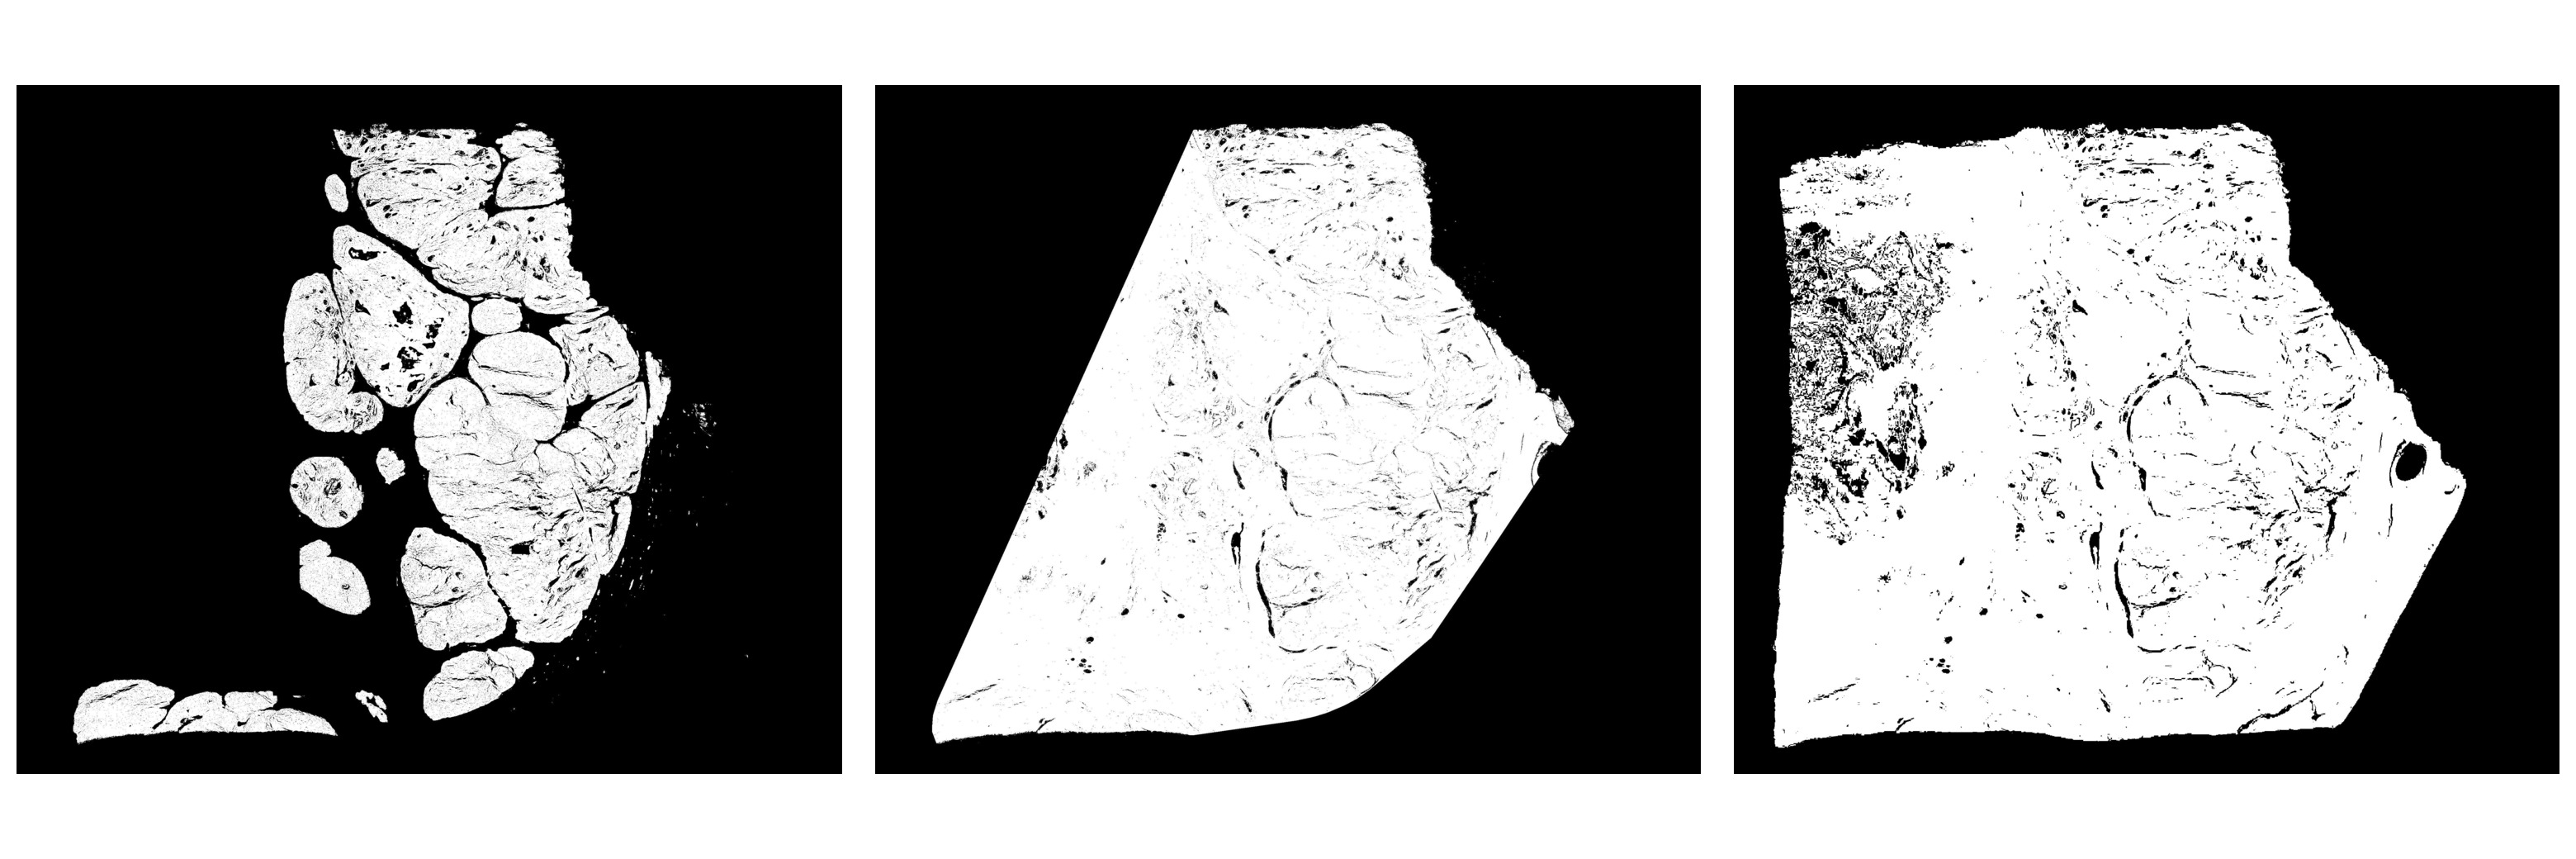

3.3.2 Tissue mask generation specific to CAMELYON dataset

In some of the CAMELYON17 cases, the Otsu’s thresholding failed because of the black regions in the whole slide image. Hence, before the application of image thresholding operation, the pre-processing involved replacing black pixel regions in the whole slide image back-ground with white pixels and median blurring with a kernel of size 7x7 on the entire image. Median blur aided in the smoothing of the tissue regions and removal of noise at the tissue bordering the glass-slide region while preserving the edges of the tissue. Figure 3 illustrates the pipeline for tissue mask generation with an example.